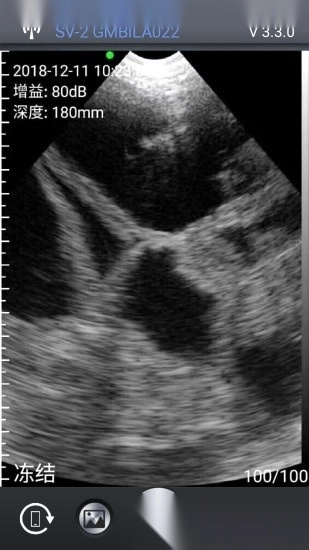

该应用可与指定品牌的无线兽用B超仪快速建立连接,随后在软件内清晰呈现诊断细节与结果。它致力于为养殖工作者提供优质服务,使得掌握猪群健康状况变得简单快捷。应用安装后,成功配对硬件设备即可开始检测,流程顺畅高效。软件还集成了多项实用功能,满足日常养殖的多种需求。

3、通过专用无线网络即可完成连接,并在应用中观察图像;

2、提供多种结果查看模式,用户可根据实际需要自由选择;